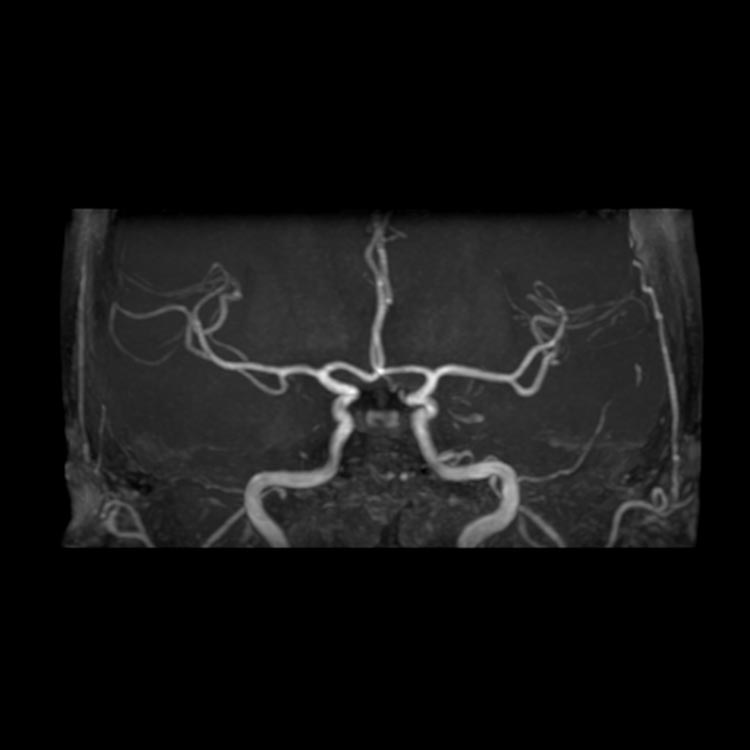

MRI:正常な脳の画像と脳の血管